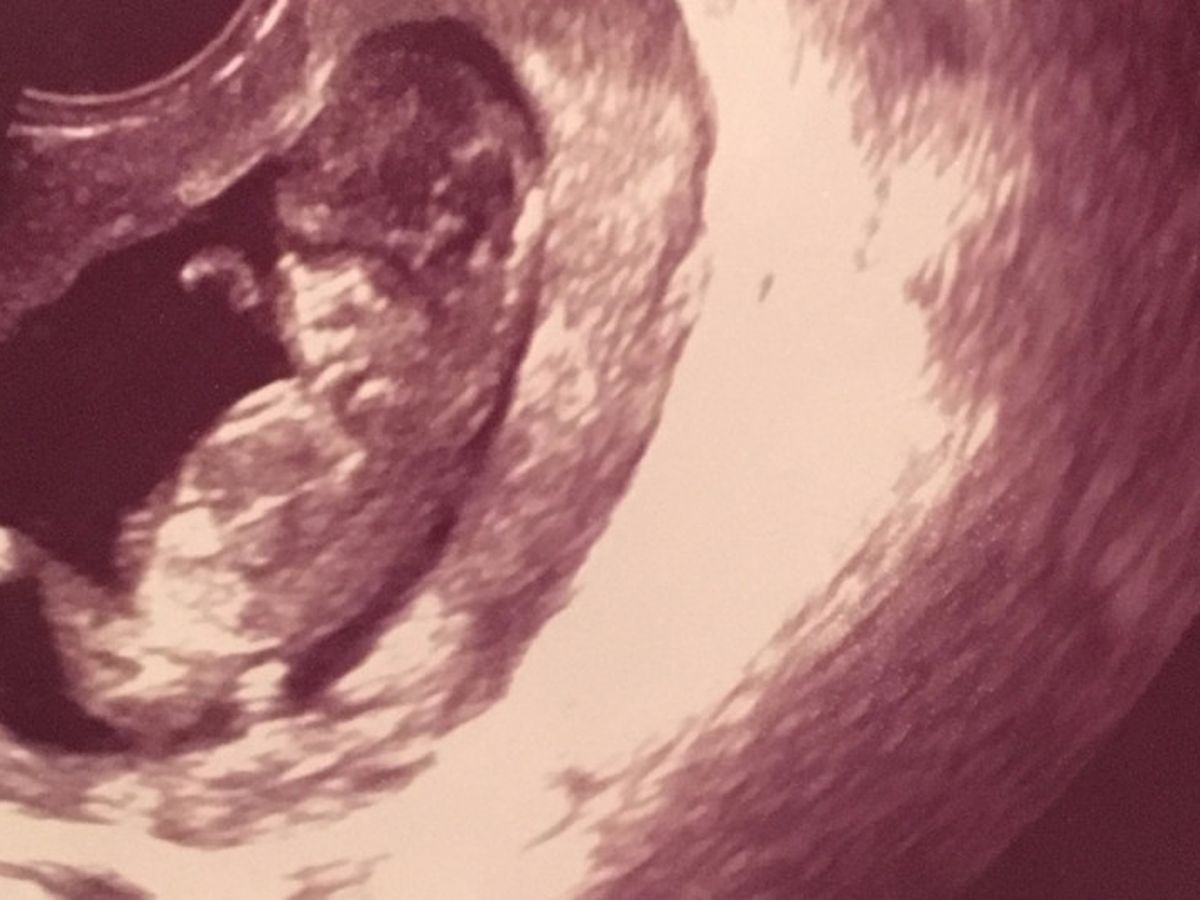

My family and I are asking for a little help, and this is something we never really do. We are more likely to help and ask for nothing in return.  My little sister Lea and her boyfriend Chris are expecting there second child, another little girl.  In April they were told she will be born with Spina Bifida. In short Spina Bifida is when the spinal cord does not close and is exposed.  Baby has been diagonsed with the most severe form of Spina Bifida called myelomenigocele.  We will not know what type of disabilites she will be born with.  We do know the day after she is born a surgery will be performed to close the spinal cord, and there is also a possibilty of shunts being put in her head to drain fluid to prevent any brain damage.  She will then spend the first month of her life in the NICU.  Baby will be will be here in August and Mom and Dad will need some help. Any donations will go to medical bills, hotel stays (the hospital is an hour and half away from home), and any special equipment needed to care for baby.  Please donate and help my family. Every dollar is greatly apprciated